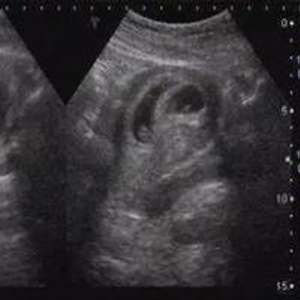

早孕期孕囊里包裹的除了胚芽还有一些羊水。我们可以想象一下,兜着水的气球,放在桌子上会变成什么形状。孕囊就是这种不规则的类椭圆体。

孕期,不管是腹壁B超还是经阴道B超,都是无法做到三维重建,只能根据超声检测到的2-3个径线来描述孕囊的大小。大家拿到手的B超报告,数值接近的,容易被理解为是圆形,有的数值差距太大,就被理解为椭圆形。

超声看到的是形态上的影像,当胎儿的外生殖器长到可以通过超声看到的程度,就可以进行检查了。一般需要怀孕3-4月以后了,不过误差也比较大。更何况,我们国家法律明令禁止孕期看性别,所以,你就别想啦。